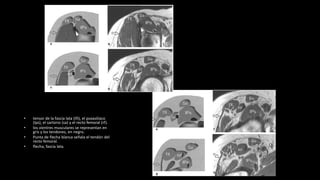

• tensor de la fascia lata (tfi), el psoasilíaco

(Ips), el sartorio (sa) y el recto femoral (rf).

• los vientres musculares se representan en

gris y los tendones, en negro.

• Punta de flecha blanca señala el tendón del

recto femoral.

• flecha, fascia lata.

• músculos pectíneo

(Pt), aductor largo (1),

aductor corto (2),

aductor mayor (3) y

recto interno (Gr).

• ObtE, obturador

externo

• tensor dela fascia lata (tfi), el psoasilíaco (Ips), el sartorio (sa) y el recto femoral (rf). • los vientres musculares se representan en gris y los tendones, en negro. • Punta de flecha blanca señala el tendón del recto femoral. • flecha, fascia lata.

• músculos pectíneo (Pt),aductor largo (1), aductor corto (2), aductor mayor (3) y recto interno (Gr). • ObtE, obturador externo